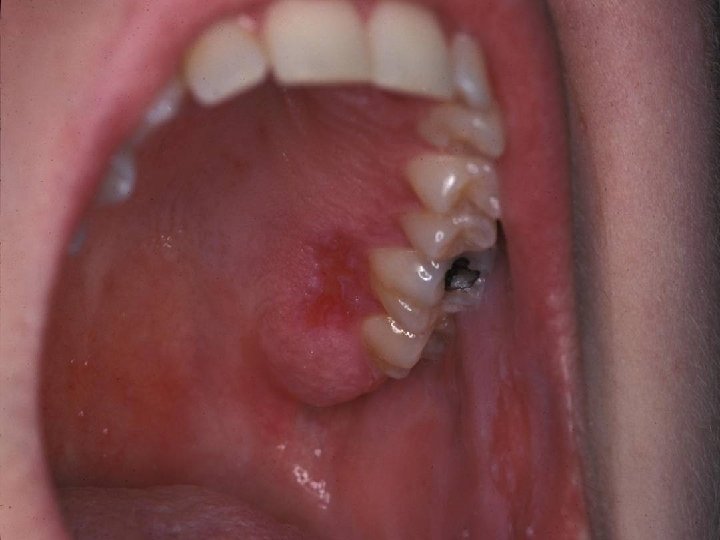

Dermatological involvement • • • Up to 85% of SLE Butterfly rash Maculopapular eruption Discoid lupus Relapsing nodular non-suppurative panniculitis Vasculitic skin lesin Livedo reticularis Purpuric lesions Alopecia Oral ulcer

• Oral ulcer: Painless sores in the nose or mouth need to be observed and documented by a doctor.